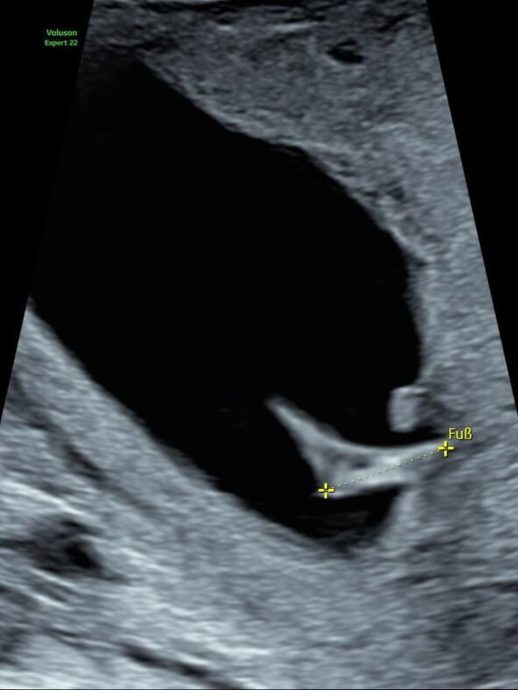

«Gracias por todas sus palabritas dichas y escritas y por el amor sostenido en el tiempo. De agradecimiento les regalo una patita intrauterina de pisada firme 🫀», concluyó.